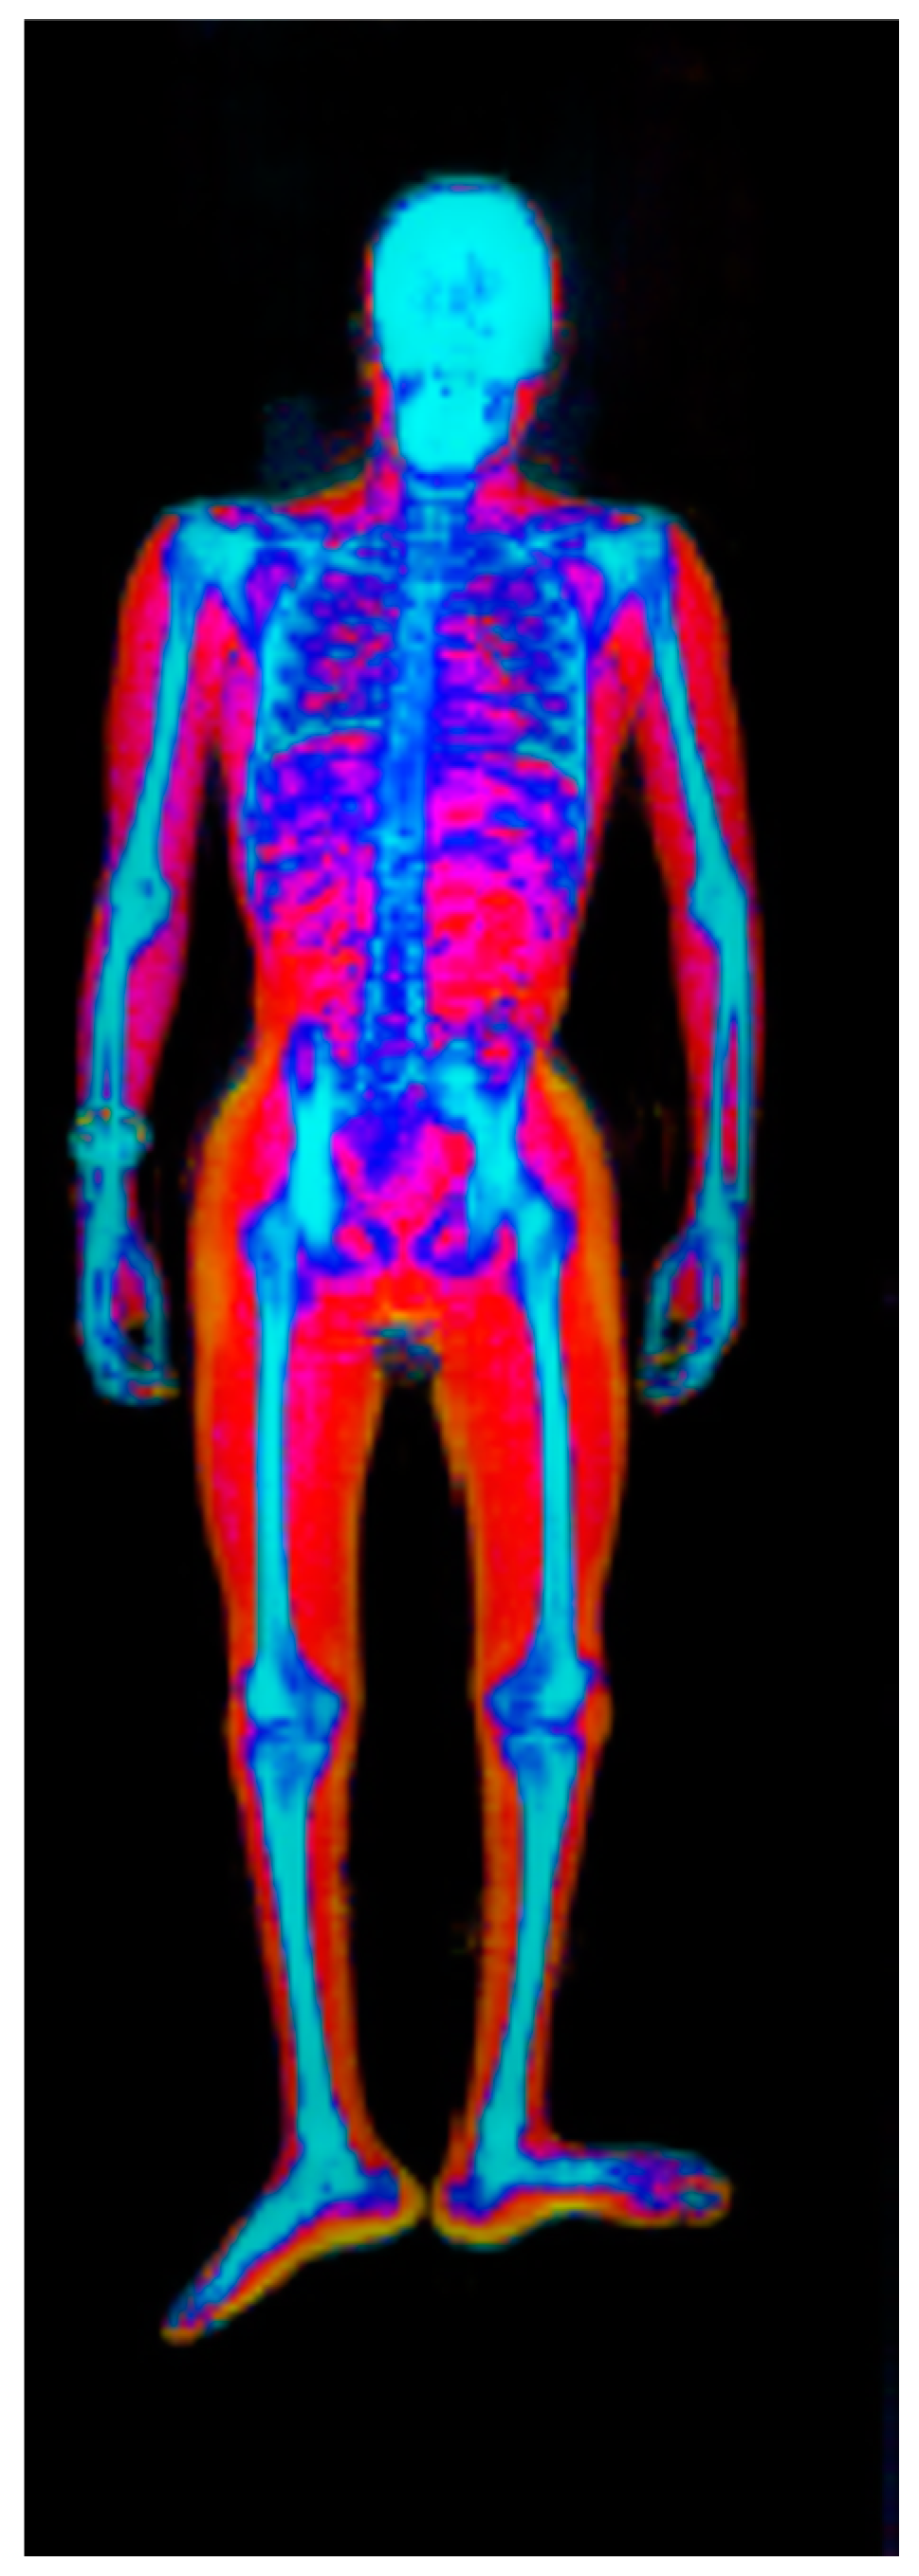

• Two-component techniques and models: dual-energy x-ray absorptiometry (DXA) (Figure 1) [20,21], air displacement plethysmography [22,23,24], deuterium dilution [25], computed tomography (CT) [21,26], and magnetic resonance imaging (MRI) [27,28].

Figure 1. Body composition by DXA.